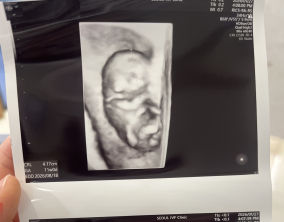

임신 수치 16, 9주차 기적의 기록